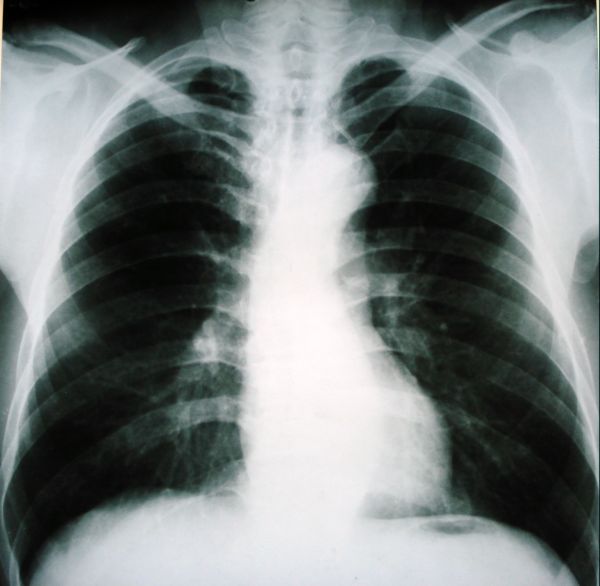

男,54岁,平时有吸烟后咳嗽、咯痰史,因右侧胸部(腋窝下)疼痛来检查平片,见右下肺动脉干起始处处结节,后到同学处做了平扫及增强。请各位老师帮忙看一下,不甚感谢!!!!!

肺窗薄扫、常规扫描均未见明确病变;右下肺门圆形与肺血管等密度影,考虑为血管变异;应该要纵隔窗才能进一步明辨。

x线表现与ct扫描相吻合。